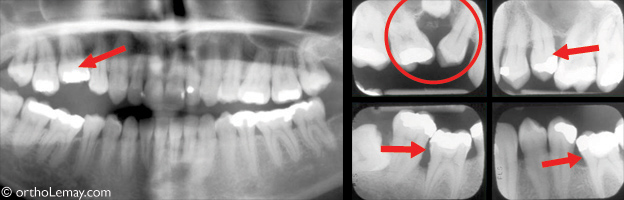

Exemples de dents postérieures ankylosées qui sont plus basses et affectent la position des dents adjacentes.

Problèmes d’éruption causés par la présence d’une dent temporaire ankylosée qui n’a pas été extraite. Voir la légende ci-dessous.

Cette femme de 28 ans présente un problème d’éruption qui aurait pu être évité avec une supervision adéquate pendant l’éruption des dents à l’adolescence.

- (A) La seconde molaire supérieure temporaire droite (* jaune) est ankylosée et est devenue progressivement submergée à mesure que les dents adjacentes ont continué à pousser et ont éventuellement dépassé la dent ankylosée pour basculer par dessus elle (flèches rouges en A, B et C).

- La seconde prémolaire (* rouge) demeure bloquée sous la dent ankylosée et ne peut continuer son éruption normale. Non seulement les dents basculées affectent l’occlusion et la fonction mais cette région est difficile d’entretien et les dents sont plus susceptibles à la carie et aux infections parodontales.

- Comparez la position de la prémolaire droite incluse sous la dent ankylosée (A) à la même prémolaire du côté opposé (D * bleu) qui elle, est sortie normalement car la dent temporaire qui la recouvrait n’était pas ankylosée et est tombée normalement au début de l’adolescence. L’extraction de la dent ankylosée et l’utilisation d’un mainteneur d’espace pendant l’éruption de la prémolaire du côté droit aurait permis à la prémolaire droite de sortir normalement comme celle de gauche.